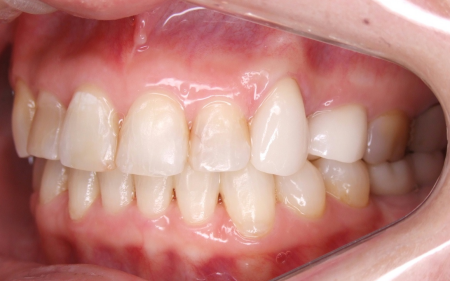

矯正治療が終了した後半年間、要素A要素B要素Dに変化がないか?安定しているか?を観察したあと、左下のインプラント2本(第1大臼歯、第2大臼歯)にはそれぞれ単独の被せ物、右下の奥歯3本(第2小臼歯、第1大臼歯、第2大臼歯)にはインプラントを土台にしたブリッジ、左上の歯3本(犬歯、第1小臼歯、第2小臼歯)には歯の大きさを調整して犬歯と第2小臼歯にそれぞれ単独の被せ物を装着しました

被せ物の素材は患者様のご希望に沿い、天然歯のような透明感があり審美性と耐久性に優れた「セラミック」を選択しています。

また、天然歯の黄ばみを改善するために、歯科医院で施術する「オフィスホワイトニング」と、ご自宅で行っていただく「ホームホワイトニング」を併用した「デュアルホワイトニング」をお口全体に施しました。 デュアルホワイトニングは短期間で理想の白さになり、色の後戻りもしにくいのがメリットです。 オフィスホワイトニングは1回、ホームホワイトニングは約3ヶ月ほど行って治療を完了しています。

インプラントを埋め込んだことで食べ物がしっかり噛めるようになりました。歯の黄ばみも改善し、歯並びも整ったことで美しい口元を取り戻しています。

患者様には「40代で入れ歯を避けることができてよかった。なんでも噛めて、コンプレックスだった見た目もきれいになってとてもうれしい」と大変ご満足いただきました。